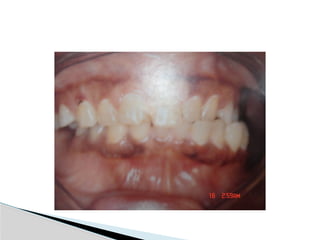

 Malocclusion

 Evidence ofST injury (Contusion, abrasions, chin laceration)  Facial asymmetry with chin deviation  Noticeable or palpable swelling over affected TMJ  Pain & tenderness over affected TMJ  Malocclusion  Deviation of mandibular dental midline  Muscle splinting due to pain with limited opening  Bleeding from EOC  Inability to palpate condylar movement Clinical signs